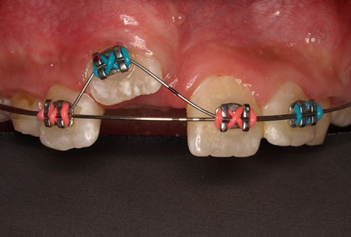

Việc kiểm soát tình trạng răng mọc chậm do răng thừa có thể được thực hiện bằng hai phương pháp. Thứ nhất, bằng cách điều trị bảo tồn, chỉ bằng cách phẫu thuật loại bỏ răng thừa (hình 4). Thứ hai, bằng cách phẫu thuật loại bỏ răng thừa kết hợp cùng lúc với chỉnh nha kéo răng cửa ngầm lên (hình 5).

Răng thừa (a) làm R11 (b) bị kẹt không mọc ra được Tạo khoảng trước phẫu thuật

Phẫu thuật lấy răng thừa sau 4 tháng tạo khoảng Chỉnh nha kéo R11 ngầm lên

Qúa trình chỉnh nha kéo răng cửa mọc ngầm hoàn tất

Hình 5: Minh họa phẫu thuật lấy răng thừa kết hợp với chỉnh nha ở một bé trai 9 tuổi